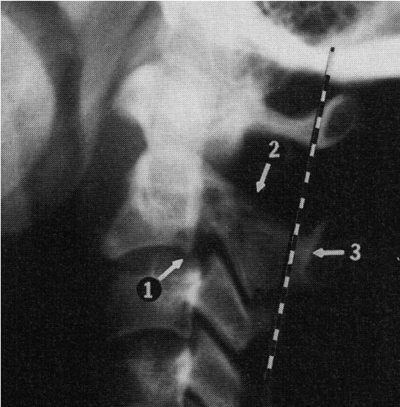

Рис. 4.3. Перелом "палача" (цит. по L. Swischuk Imaging of the Cervical Spine in Children. Springer, 2004, p. 102).

1. Тело CII смещено кпереди.

2. Перелом дуги CII.

3. Основание остистого отростка CII смещено кзади от линии Swischuk более чем на 2 мм